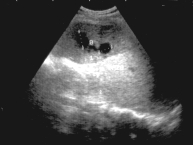

ECOGRAFIA

ABDOMINAL: En ambos riñones se advierte disminución de zona

medular - En el bazo se visualizan dos imágenes ecolúcidas

de 19 y 23 mm., en comunicación).

DIAGNOSTICO: hepatoespelnomegalia-imagen quística en bazo (Figura 1)